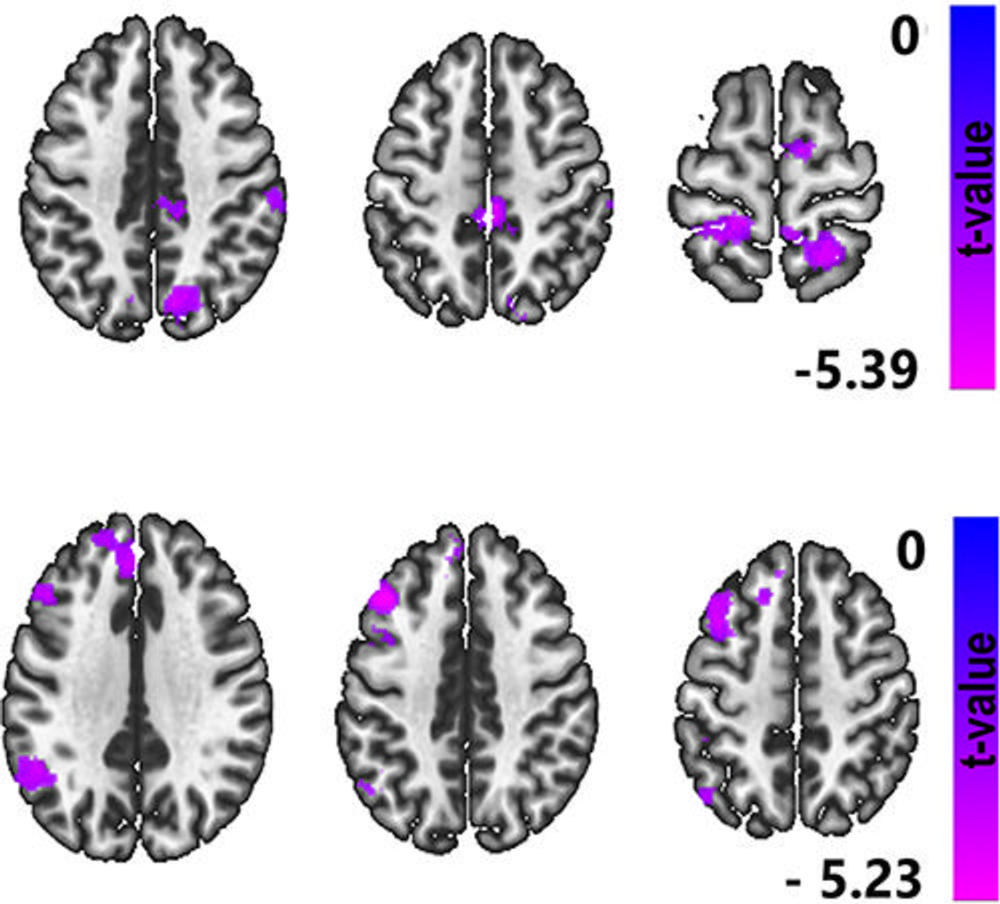

Figure 3. Functional MRI (fMRI) scans depict the merged regions of interest that showed significant differences between the high and low blast exposure groups in both dataset 1 and dataset 2. These regions of interest were combined to create a unified representation of the second-level analysis. These regions were used in the model to predict group membership solely based on fMRI data. The clusters involved the bilateral superior and inferior lateral occipital cortex, the frontal medial cortex, left superior frontal gyrus, and precuneus.

Figure 4. Functional MRI scans highlight the effect of Neurobehavioral Symptom Inventory (NSI) score on functional MRI connectivity while controlling for median blast exposure count 5 value and using lateral occipital cortices as the reference seed. NSI demonstrates a negative correlation with functional connectivity between the seed regions (lateral occipital cortices) and a cluster centered in the left superior parietal lobule, suggesting that higher symptom severity is linked to weaker communication between these brain regions.

Figure 5. Functional MRI (fMRI) scans highlight the effect of the Posttraumatic Stress Disorder Checklist for Diagnostic and Statistical Manual of Mental Disorders (Fifth Edition) (PCL-5) score on fMRI connectivity while controlling for blast exposure count 5 value using as the reference seeds the precuneus (top row) and default node networks (DMNs) (posterior cingulate cortex, lateral parietal left, lateral parietal right, medial prefrontal cortex) (bottom row), suggesting that greater posttraumatic stress disorder symptom severity is associated with weaker connections in brain regions involved in attention, memory, and emotional regulation. Pearson correlation analysis showed that NSI is negatively correlated with functional connectivity (FC) between superior lateral occipital cortices (LOCs) and regions involving precuneus, right supramarginal gyrus, and bilateral pre- and post-central gyrus. Furthermore, PCL-5 is negatively correlated with FC between the DMNs (posterior cingulate cortex, lateral parietal left, lateral parietal right, medial prefrontal cortex) and areas involving the left superior LOC, left angular gyrus, and left supramarginal gyrus, as well as left frontal pole and paracingulate areas.